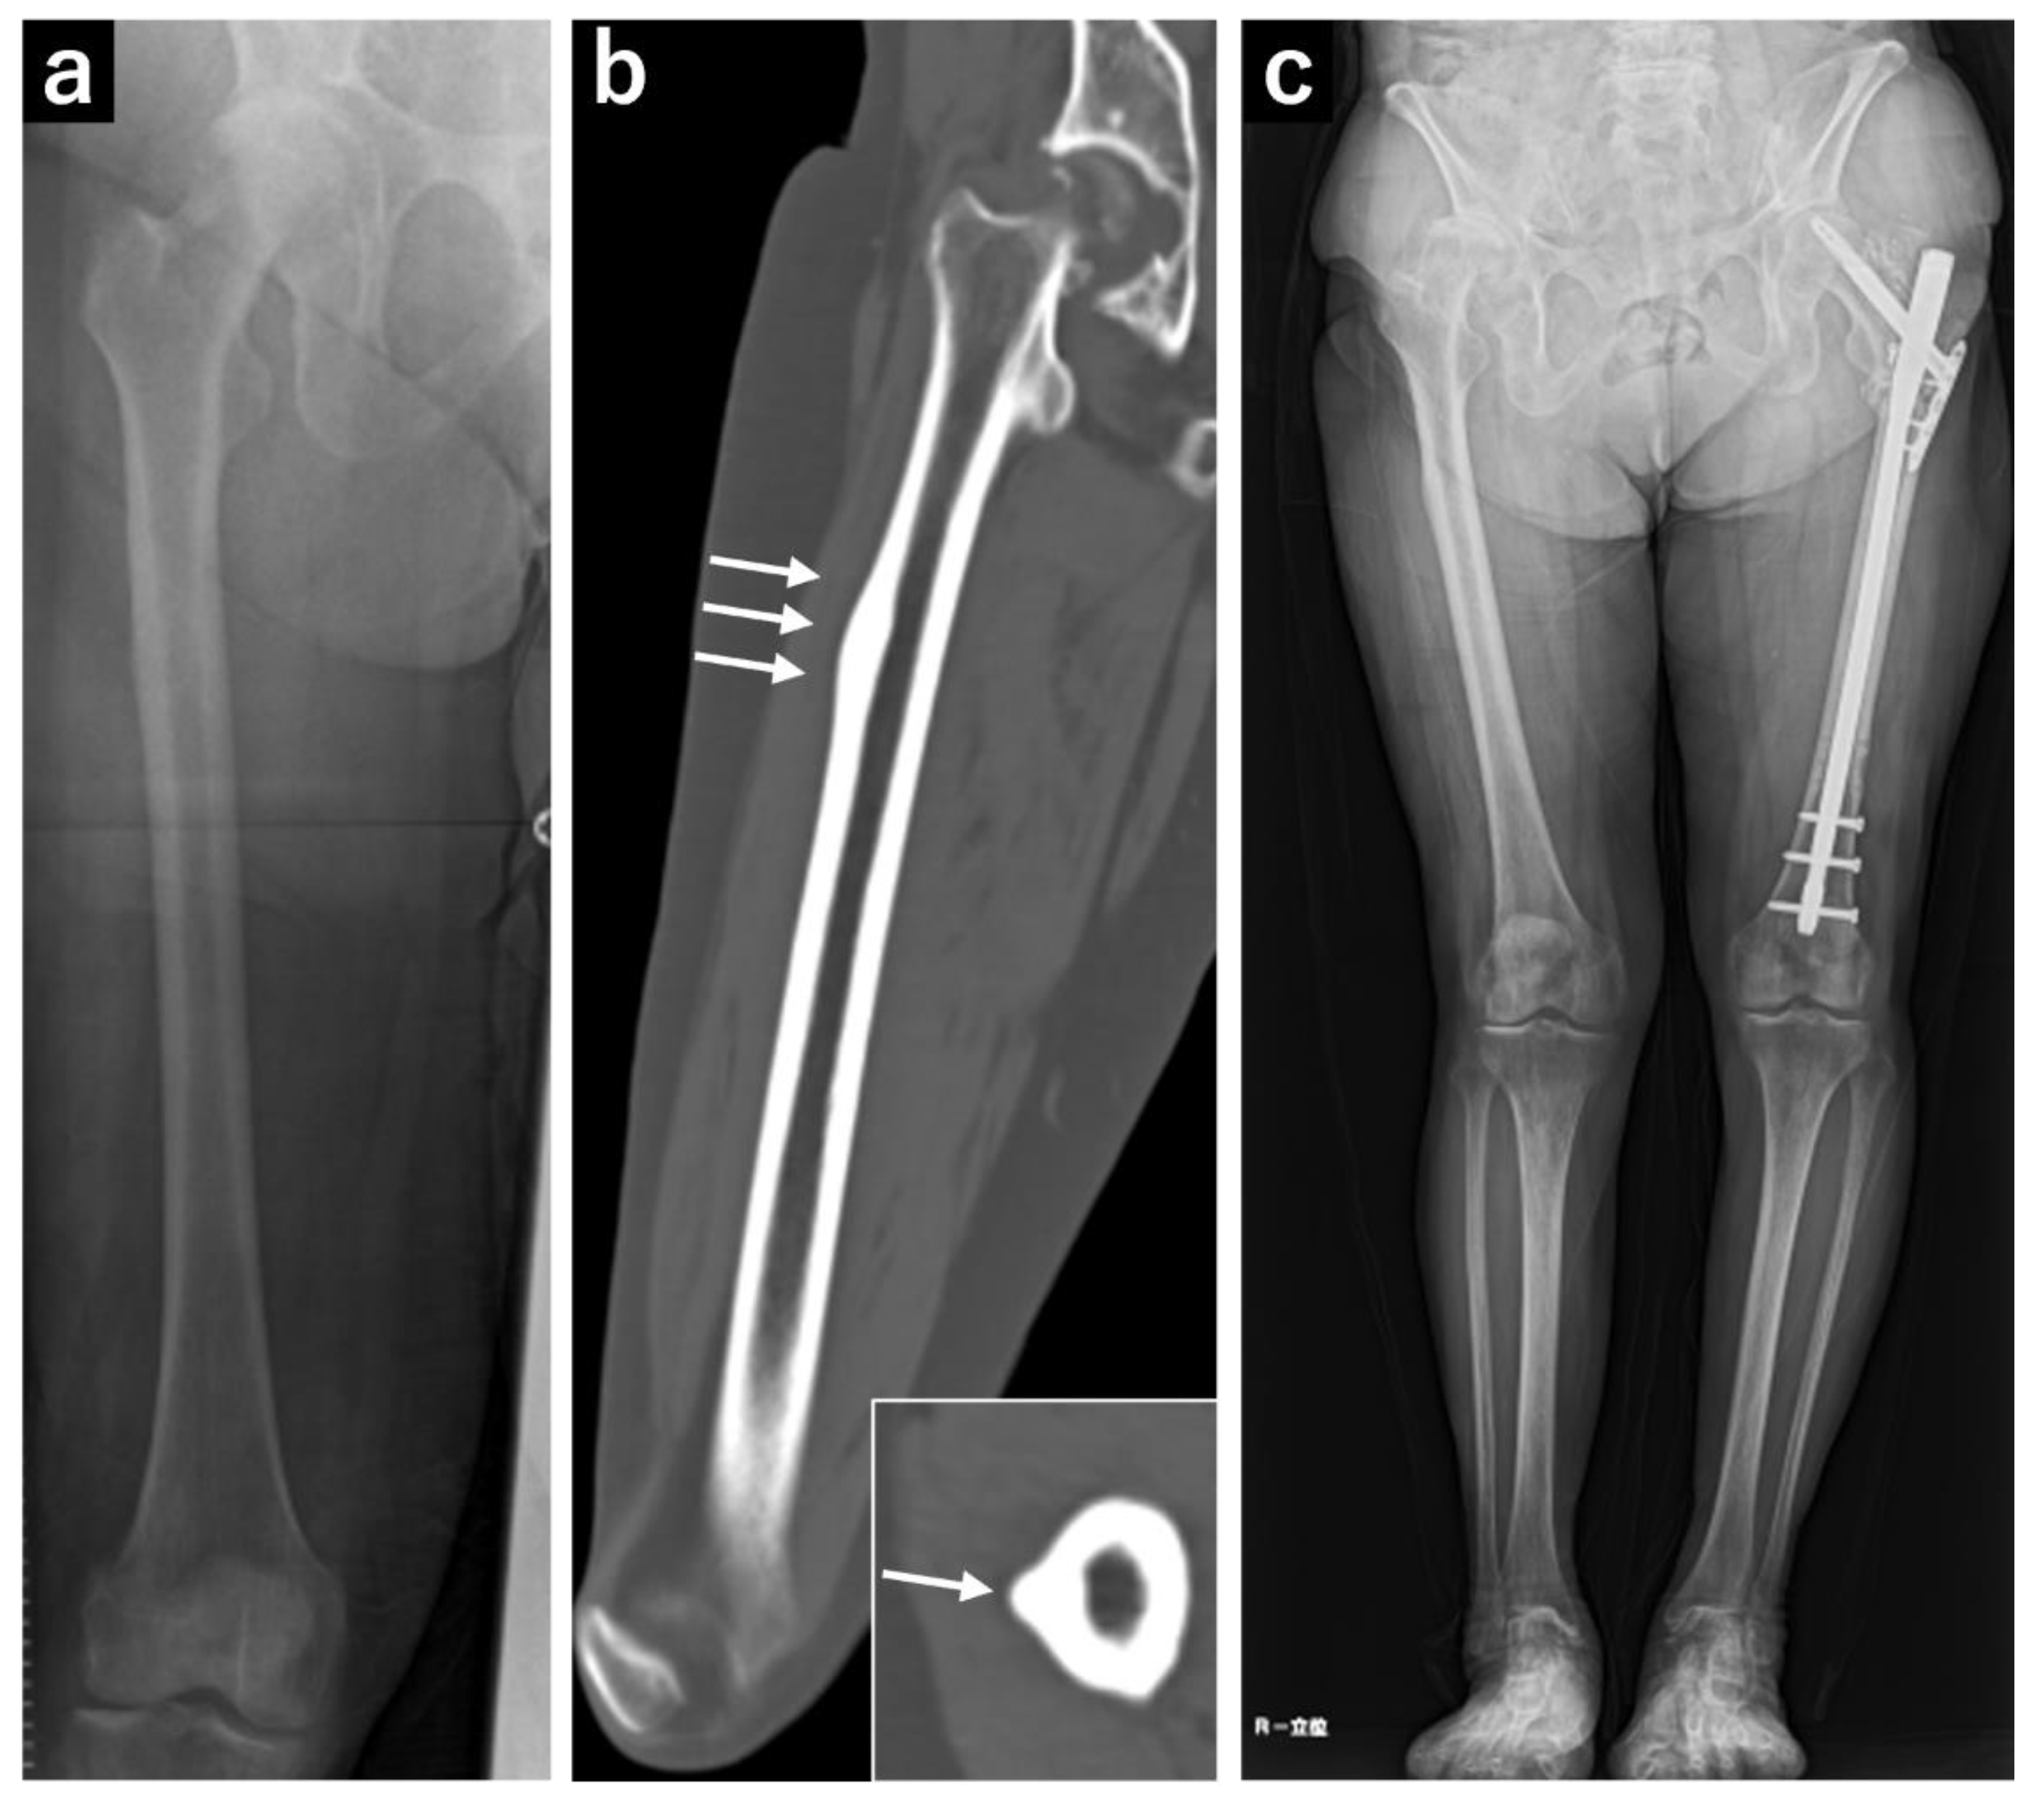

At 73 years of age, the patient experienced a fall and was diagnosed with a left subtrochanteric AFF based on plain radiography and computed tomography (CT) findings. Additionally, localized lateral cortical thickening was observed in the ipsilateral subtroschanteric region, along with osteoarthritis of the right hip (Figure 1). The patient underwent open reduction and internal fixation with an intramedullary nail for the left subtrochanteric AFF. Alendronate was discontinued, and treatment comprising 600 µg teriparatide (recombinant) was initiated, which was continued for 2 years. Due to nonunion at the fracture site, the patient underwent surgery for pseudarthrosis at 75 years of age (Figure 2). Given the gradual worsening of the right hip osteoarthritis, THA was planned when the patient turned 78 years of age.

Figure 2. Plain radiograph and computed tomography (CT) images of the right femur. (a) Plain radiograph showing localized cortical hypertrophy at the subtrochanteric region. (b) Plain CT image showing no obvious radiolucent lines. (c) A full-length plain radiograph of the lower limbs showing no significant femoral bowing deformity.